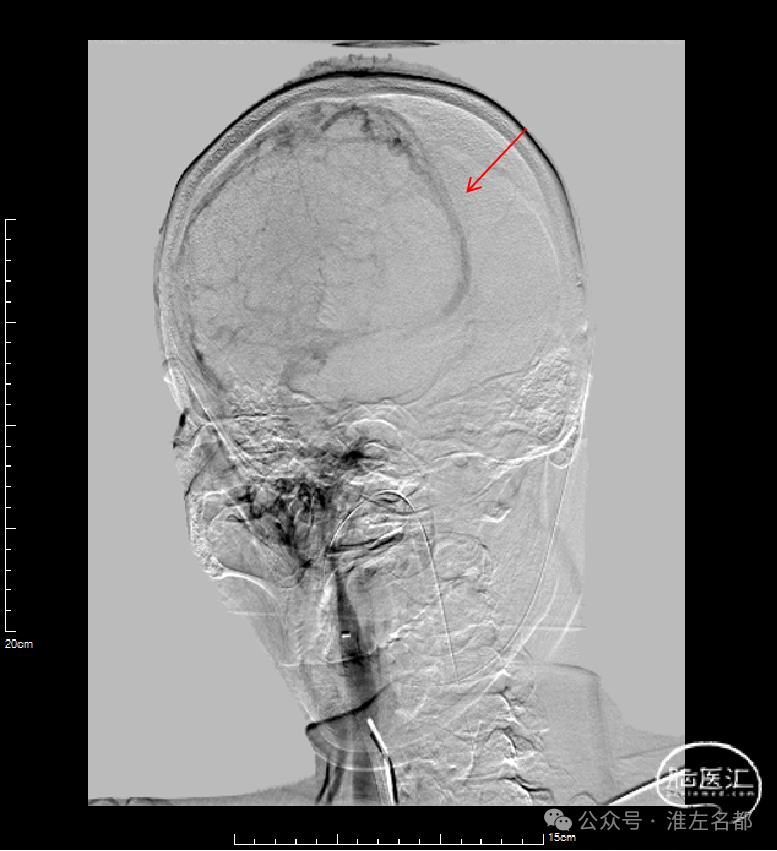

右侧颈动脉造影(正侧位):上矢状窦和直窦未见显影;右侧横窦和乙状窦少许显影。

左侧颈动脉造影(正侧位):上矢状窦前部少许显影,直窦未见显影,左侧横窦和乙状窦显影纤细。